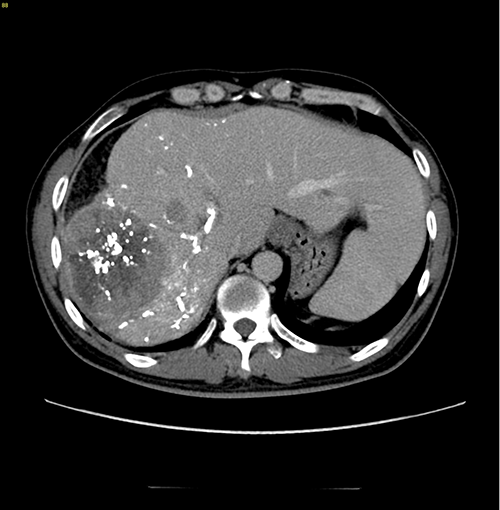

右肝巨大肝癌---右半肝切除